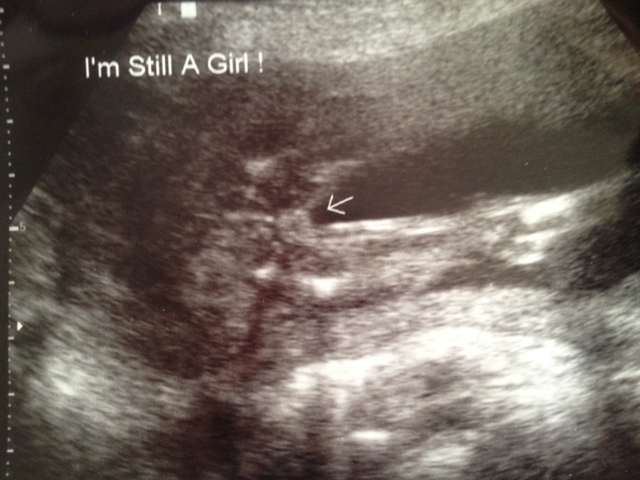

Potty shot at 16w0d

Attachment 2765